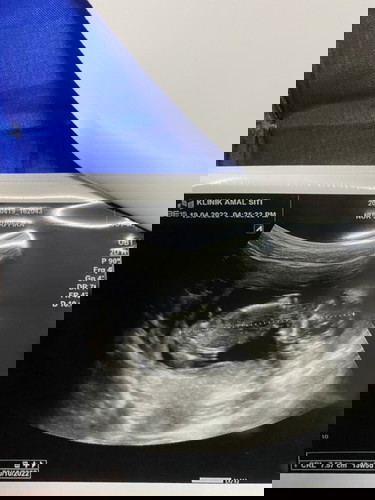

hamil 13 minggu 5 hari

alhamdulillah scan baby harini tadi rasa excited tgk baby aktif gerak2 . tapi perut saya still nampak mcm tak mengandung . lepastu doc scan dia ckp nampak mcm baby boy sbb dia punya tu nampak jelas bediri tegak sikit . lepastu doc suroh repeat scan balik masa 3 minggu nnti β€οΈβ€οΈ kalau pregnant 13weeks mcm ni dh boleh nmpak ka jantina dia ? doc asyik cakap saya rasa anak awak babyboy . #firstmom